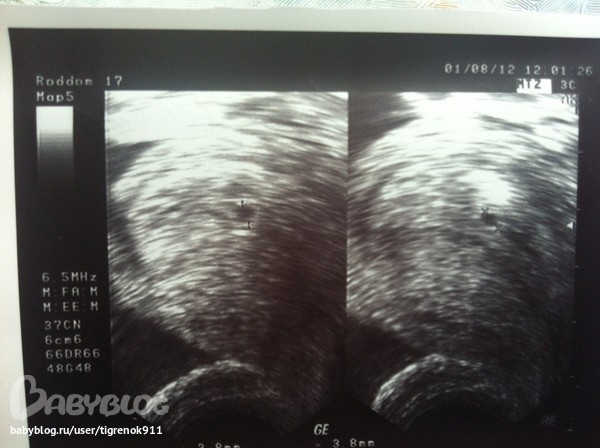

И фоточки мои красотуль!

4-5 недель: